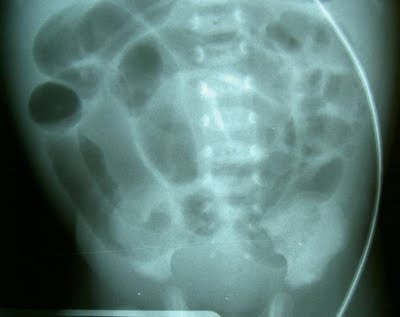

Bacterias intestinales anormales en los bebés prematuros se pueden encontrar días antes del inicio de la enterocolitis necrotizante (NEC) encuentra una nueva investigación en BioMed Central Microbioma acceso diario. Los bebés que más tarde desarrollaran NEC tenían una menor diversidad de bacterias intestinales 4-9 días después del nacimiento, el aumento de nivel de Firmicutes o Enterobacteriaceae, y carecía de la Propionibacterium encontrado en bebés sanos.

NEC es un problema frecuente pero devastador en los bebés prematuros – que afecta a cerca del 10% de los lactantes nacidos a menores de 29 semanas, alrededor de un tercio morirá.

Los bebés que llegaron a desarrollar NEC tenían una menor diversidad de organismos intestinales entre los días 4-9 después del nacimiento. Todos los bebés con NEC también tenían niveles inusuales de bacterias específicas. Los bebés cuyas NEC comenzó temprano (entre 7-12 días después del nacimiento) tenían niveles anormalmente elevados de Firmicutes mientras que los bebés cuyas NEC comenzó más tarde (19-31 días) tenían altos niveles de enterobacterias.

Todos los bebés afectados carecían de Propionibacterium generalmente en bebés sanos. Los niveles de bacterias en el presente estudio se analizaron muestras de heces. Pero los niveles de bacterias en el intestino también se puede determinar indirectamente a partir de la orina.

Prof Ardythe Morrow, quien dirigió el estudio explicó: «Nuestros datos muestran que la aparición de ECN parece estar relacionado con tener niveles anormalmente altos de bacteria en el intestino durante la primera o segunda semana de vida. Nuestros datos también indican que una orina simple probar buscando en los niveles de alanina e histidina, que aparecen alteradas por estas bacterias, se puede utilizar temprano en la vida para identificar a los bebés con riesgo de NEC.